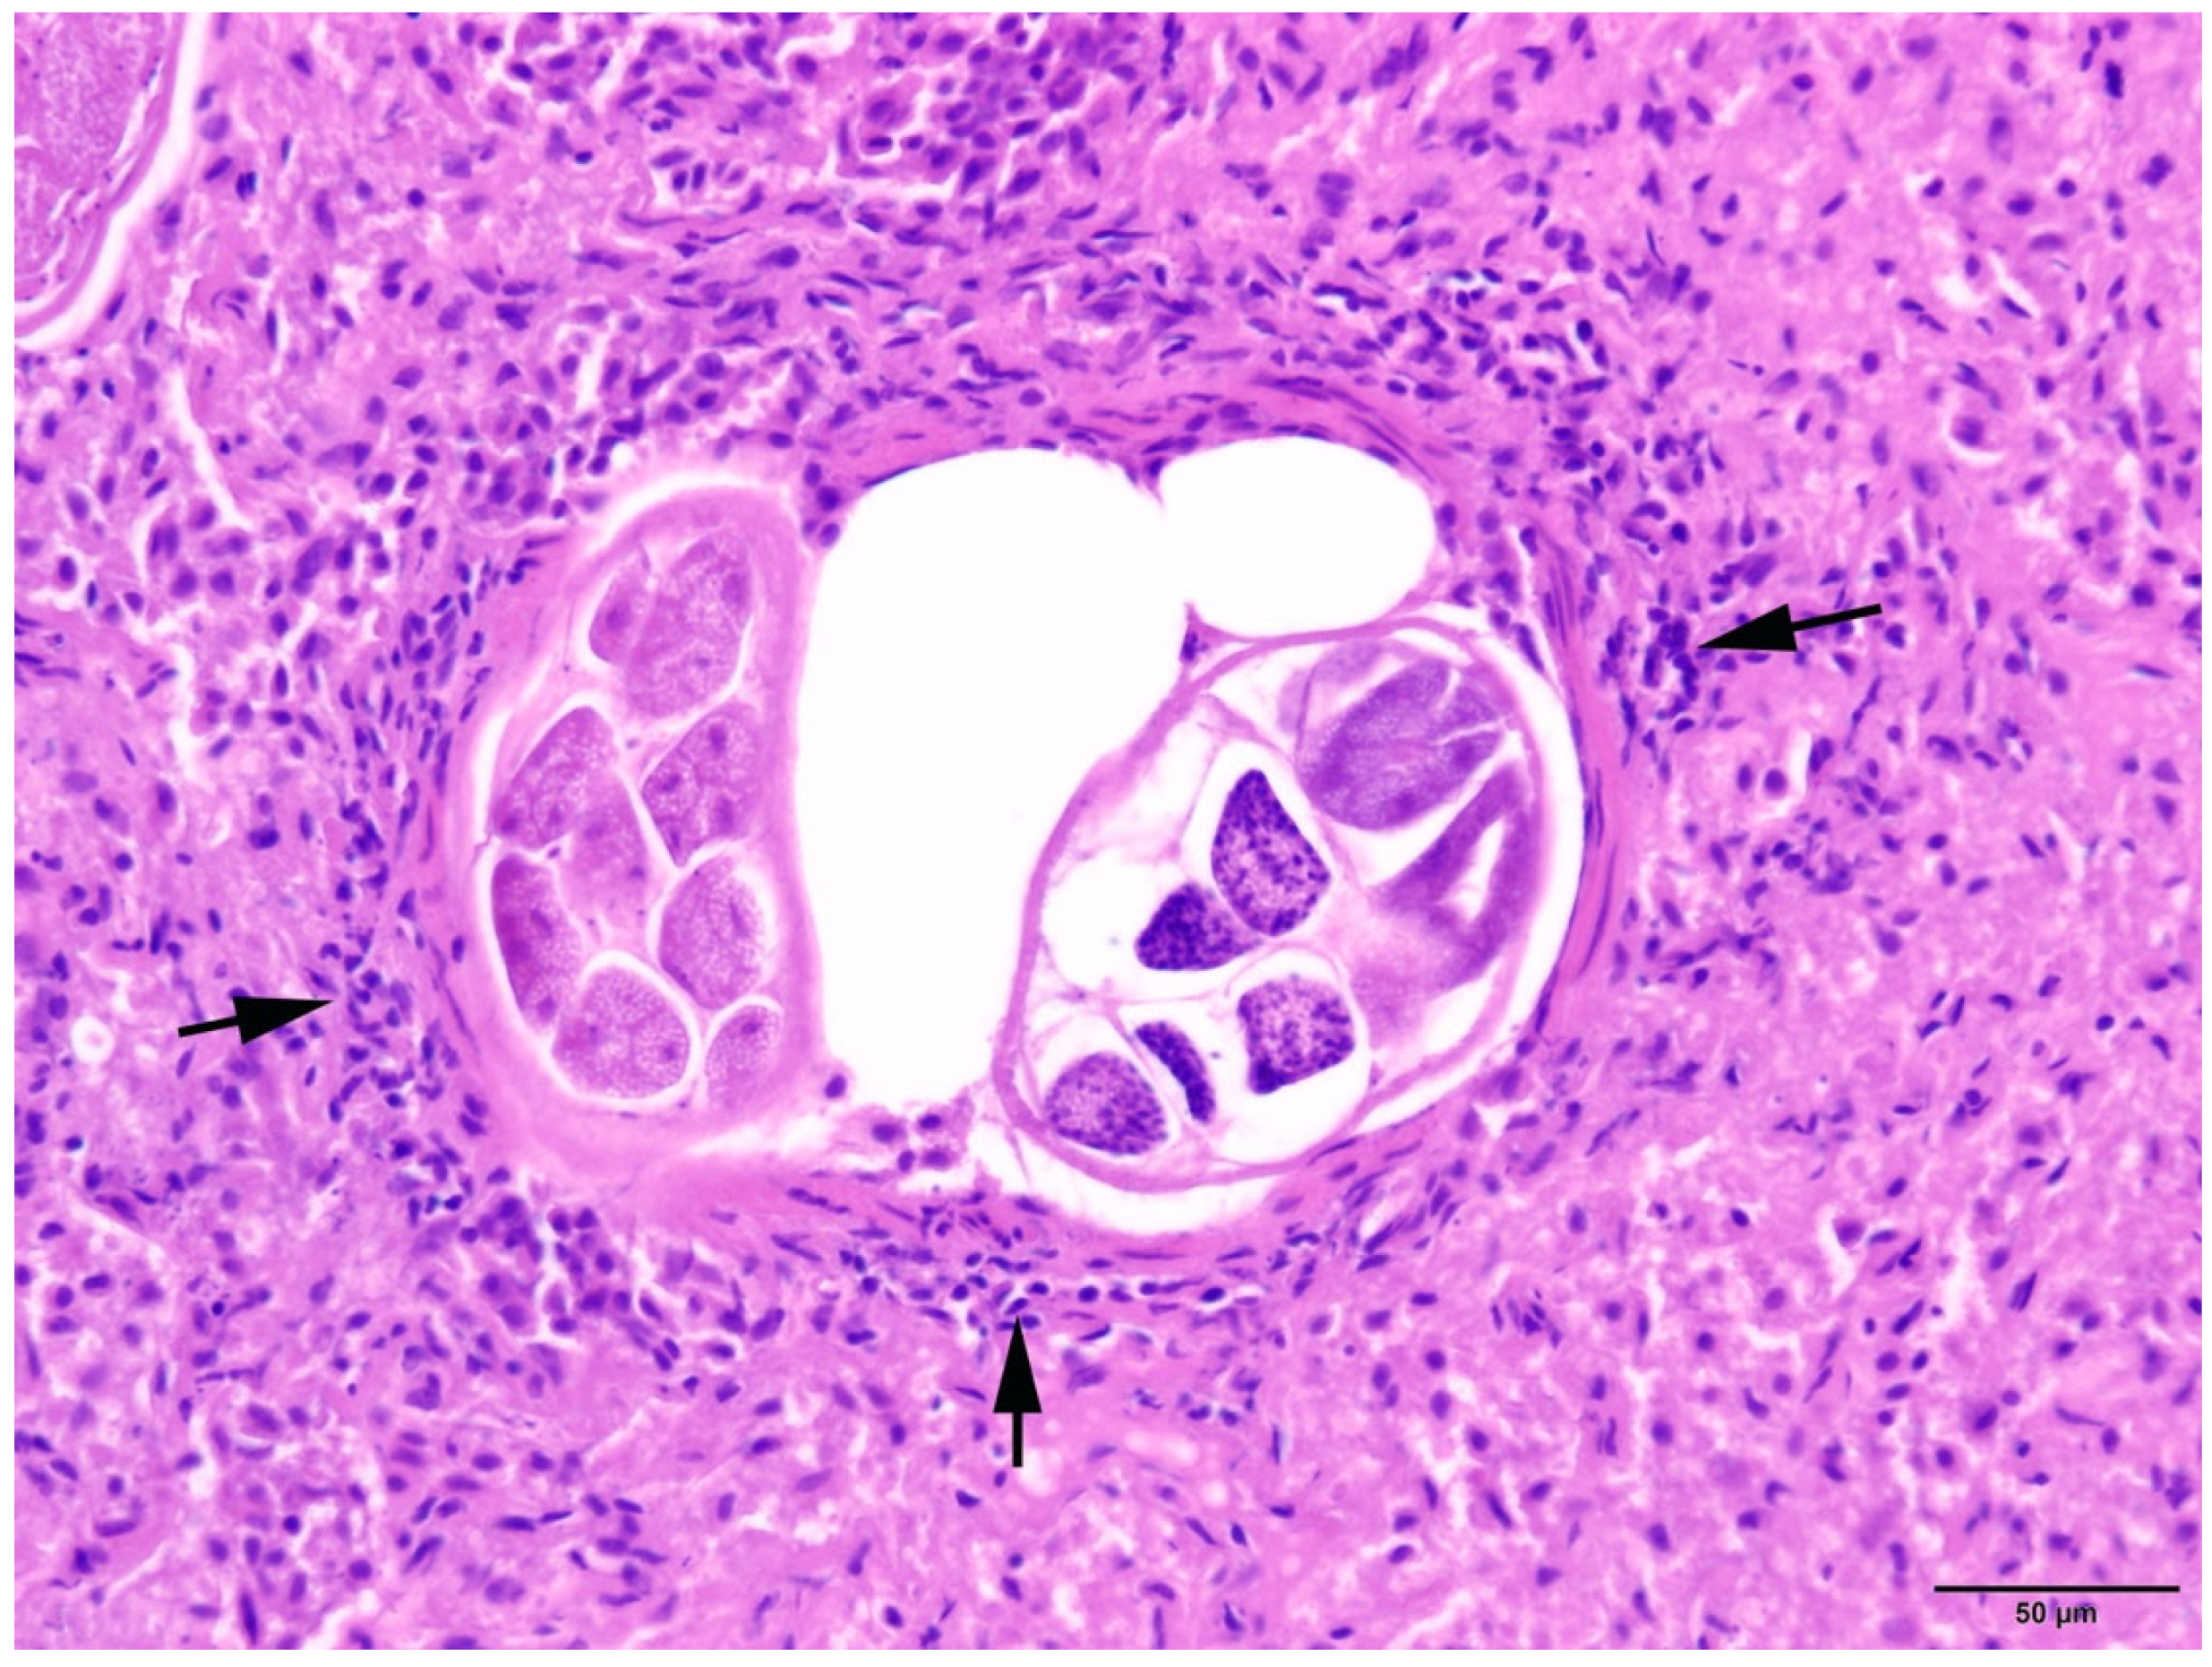

Figure 8.

Harbour seal, lung: Bronchiolus with intraluminal nematodes and mild chronic peribronchitis (arrows). HE (20×).